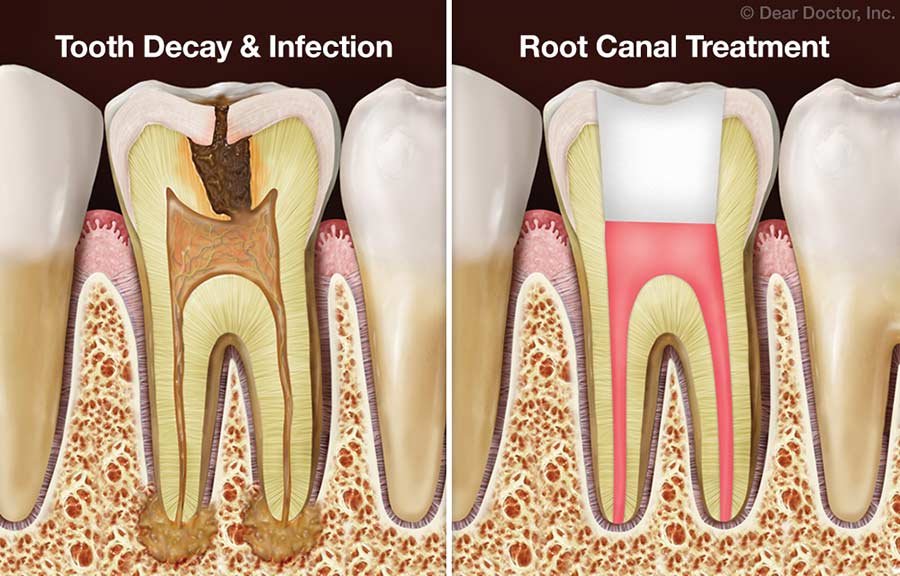

Root Canal Treatment

Root canal treatment removes infection from inside the tooth while preserving its natural structure.